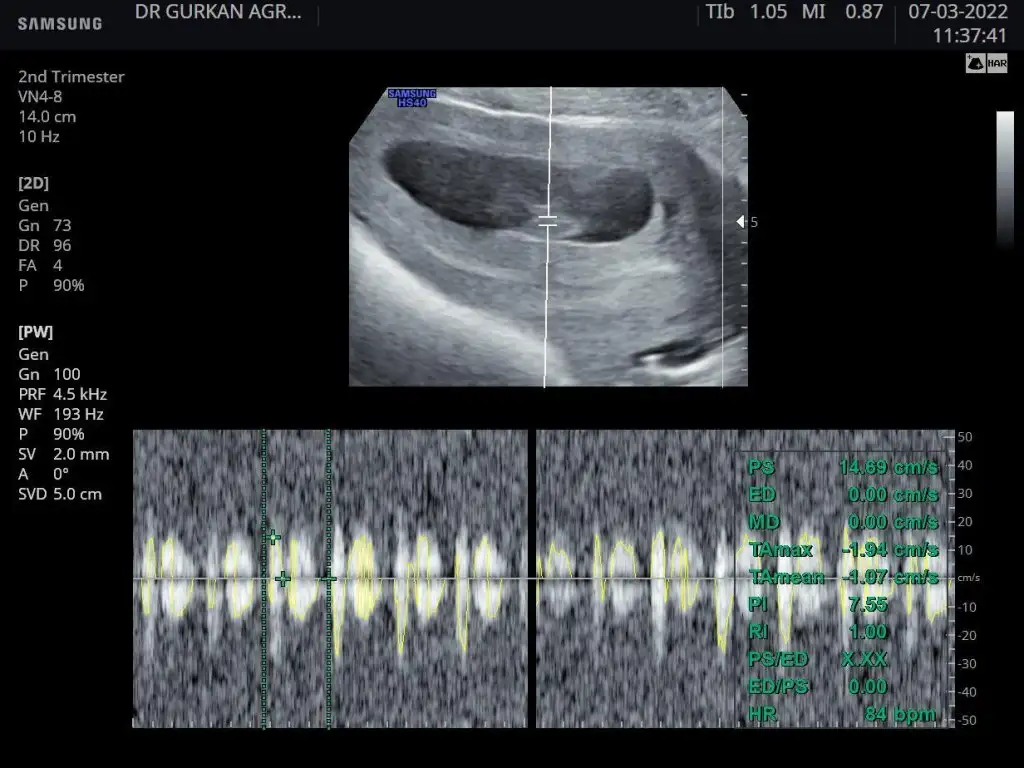

canım tahmin için biraz büyük, görüntü erkek diyor sankiMerhaba 13+0 ultrason görüntüsüne göre ben de tahmin alabilir miyim?